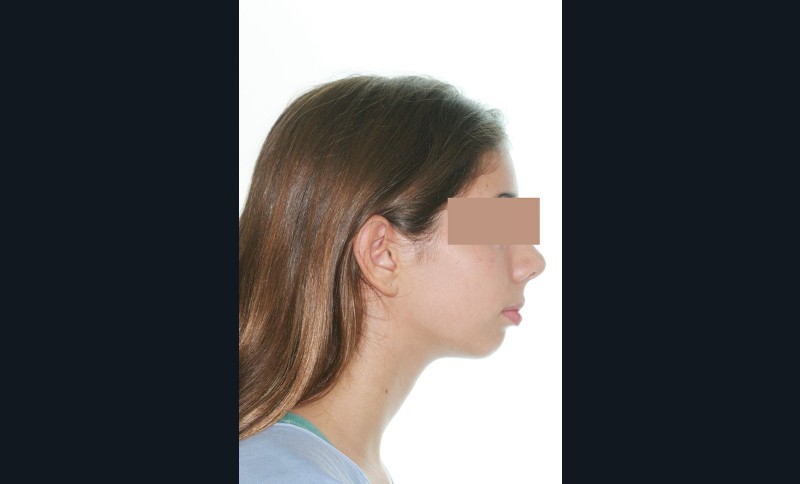

Nous sommes en présence d’une patiente adolescente âgée de 12 ans ½ dans une phase de croissance faciale favorable.

Elle présente une classe II squelettique par rétrognathie mandibulaire et une classe II dentaire molaire et canine droite et gauche associée à une biproalvéolie incisive maxillaire et mandibulaire.

L’environnement vertical est normodivergent.

Le contexte facial est délicat avec un profil cis-frontal, un angle naso-labial très ouvert et un sillon labio mentonnier marqué avec retour de la lèvre inférieure en arrière des incisives maxillaires.

Le pronostic de correction de la classe II est favorable mais il est très important de souligner la vestibuloversion incisive mandibulaire et le risque parodontal associé (fig. 1 à 3).